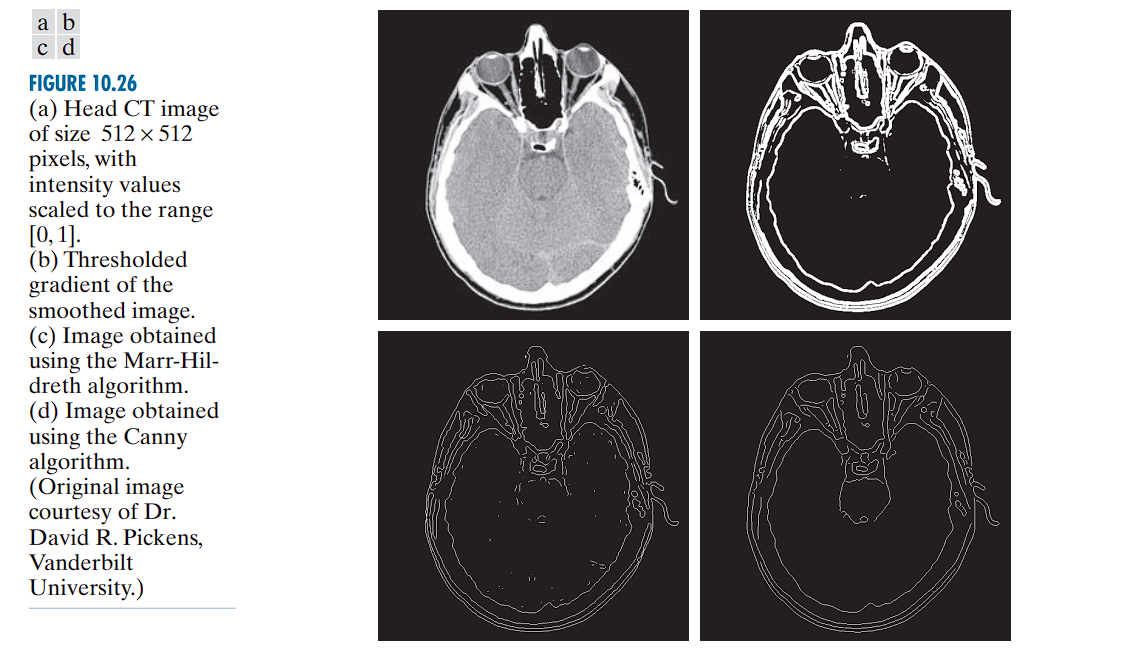

The Marr-Hildreth Edge Detector: Principle and Implementation

The edge-detection methods previously discussed rely on simple filtering operations using fixed-size convolution kernels. While computationally efficient, these basic methods do not account for edge characteristics or image noise.

The Marr-Hildreth method, introduced by Marr and Hildreth (1980), is one of the earliest attempts to embed a deeper understanding of visual perception into computational edge detection. The two central insights motivating their approach are:

Marr-Hildreth Edge Detection Algorithm

The algorithm proceeds in three main steps:

The Canny Edge Detector

The Canny edge detector (Canny, 1986) is a multi-stage algorithm designed to produce optimal edge detection results based on three primary objectives: